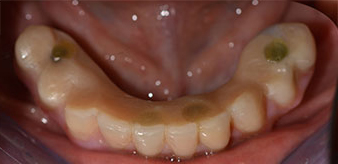

Die 64-jährige Patientin wurde mit einer Unterkiefer-Restbezahnung 38, 33 und 43 und einer klammerbefestigten Interimsprothese im Unterkiefer vorstellig (Abb. 1 und 2).

Die notwendige parodontologische Behandlung und Extraktion im Oberkiefer sollte zu einem späteren Zeitpunkt erfolgen, da die Patientin Lehrerin ist und zu dem Zeitpunkt mit Abiturprüfungen beschäftigt war. Sie konnte weder essen noch adäquat sprechen, da die Interimsprothese sehr häufig und bei der kleinsten Belastung brach.

Nach der Aufklärung über die verschiedenen Möglichkeiten der Versorgung entschied sich die Patientin für eine Extraktion der Restbezahnung im Unterkiefer, eine Sofortimplantation und Versorgung mit der sogenannten Fast & Fixed-Methode (bredent medical). Hierbei wird der provisorische festsitzende Zahnersatz bereits am OP-Tag auf vier Implantaten verschraubt. Das Ziel war, die Patientin am Freitag zu operieren, sodass sie am Montag darauf an den mündlichen Abiturprüfungen teilnehmen konnte.